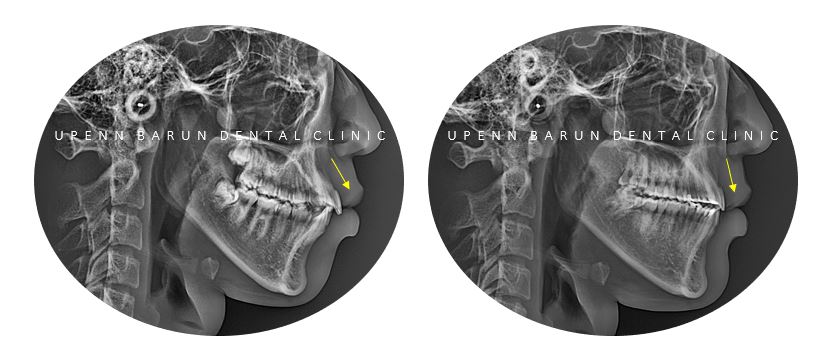

교정치료 전과 후의 엑스레이를

잠시 감상해 보시면

잠실새내치아교정

잠실발치교정 후

전과 다르게 돌출된 치아가 들어가면서

뻐드러져 있던 치축이 많이 개선되었습니다 ^^

발치교정 후

윗니와 아랫니 사이에 공간이 현저히 줄어들면서

정상적인 교합을 만들어드렸습니다 ^^